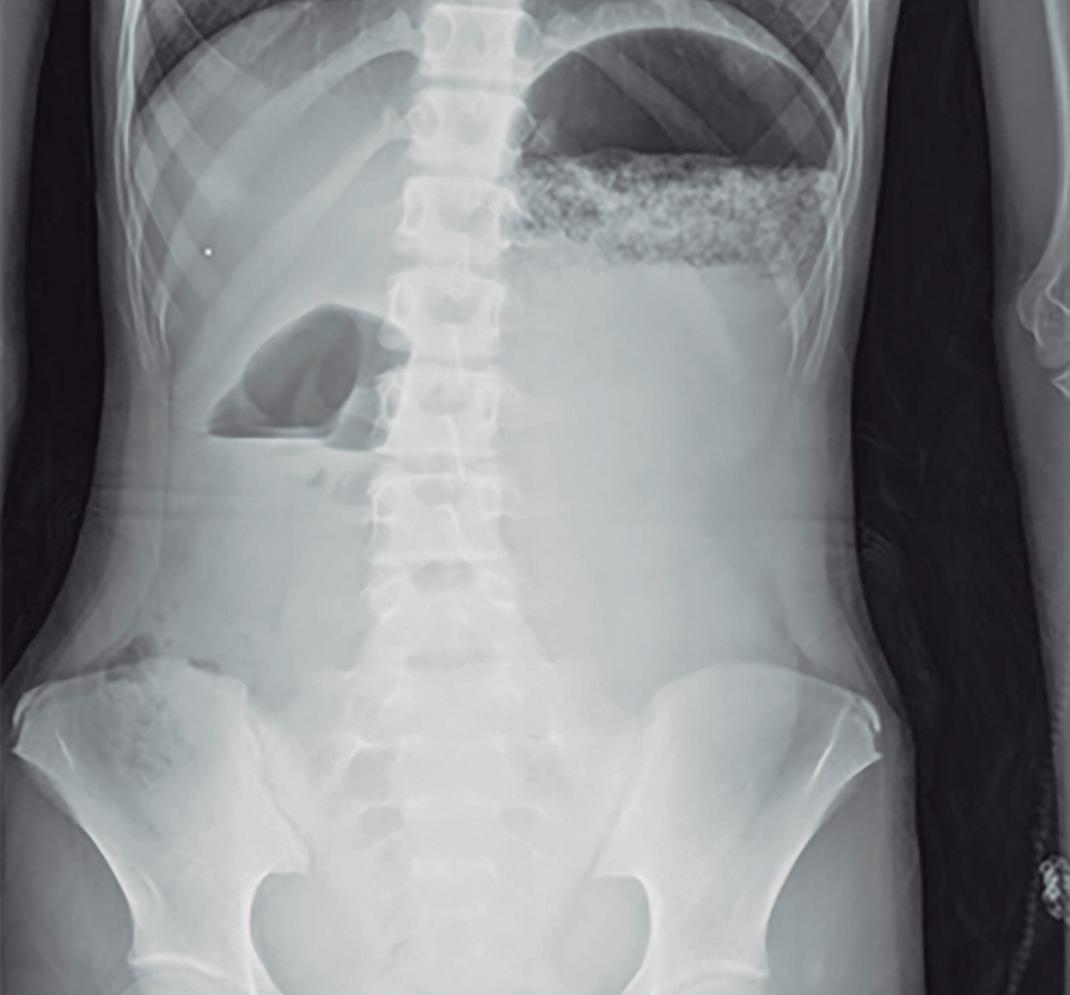

Obstrucción intestinal duodenal en una adolescente femenina

Duodenal Bowel Obstruction in a Teenage Female Patient